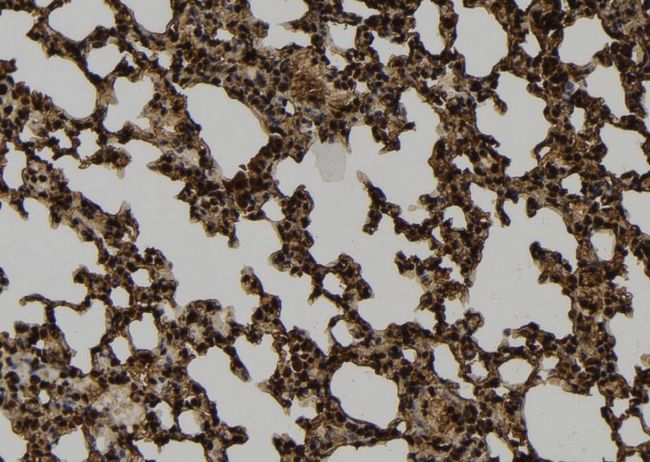

- Main image

- Experimental details

- 1:100 staining mouse lung tissue by IHC-P. The sample was formaldehyde fixed and a heat mediated antigen retrieval step in citrate buffer was performed. The sample was then blocked and incubated with the antibody for 1.5 hours at 22°C. An HRP conjugated goat anti-rabbit antibody was used as the secondary.